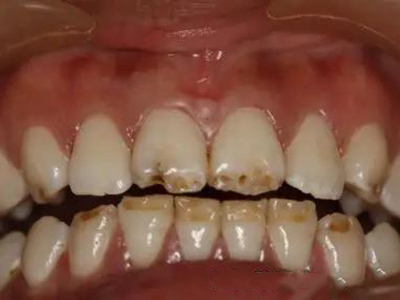

牙齿

缺损

牙釉质发育不全牙齿棕色有缺损图

牙釉质发育不全患者牙齿出现明显的缺损表现,并于表面形成深褐色的蜂窝状、竖条状的凹坑,甚至形成洞,患者上下牙失去咬合能力。